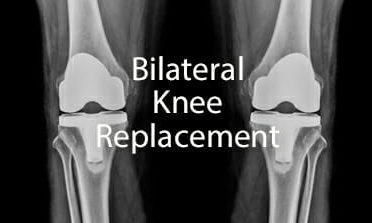

Staged Bilateral Knee Replacement Surger

Staged Bilateral Knee Replacement Surgery Cost In India

Simultaneous Bilateral Knee Replacement

Simultaneous Bilateral Knee Replacement Surgery Cost In India